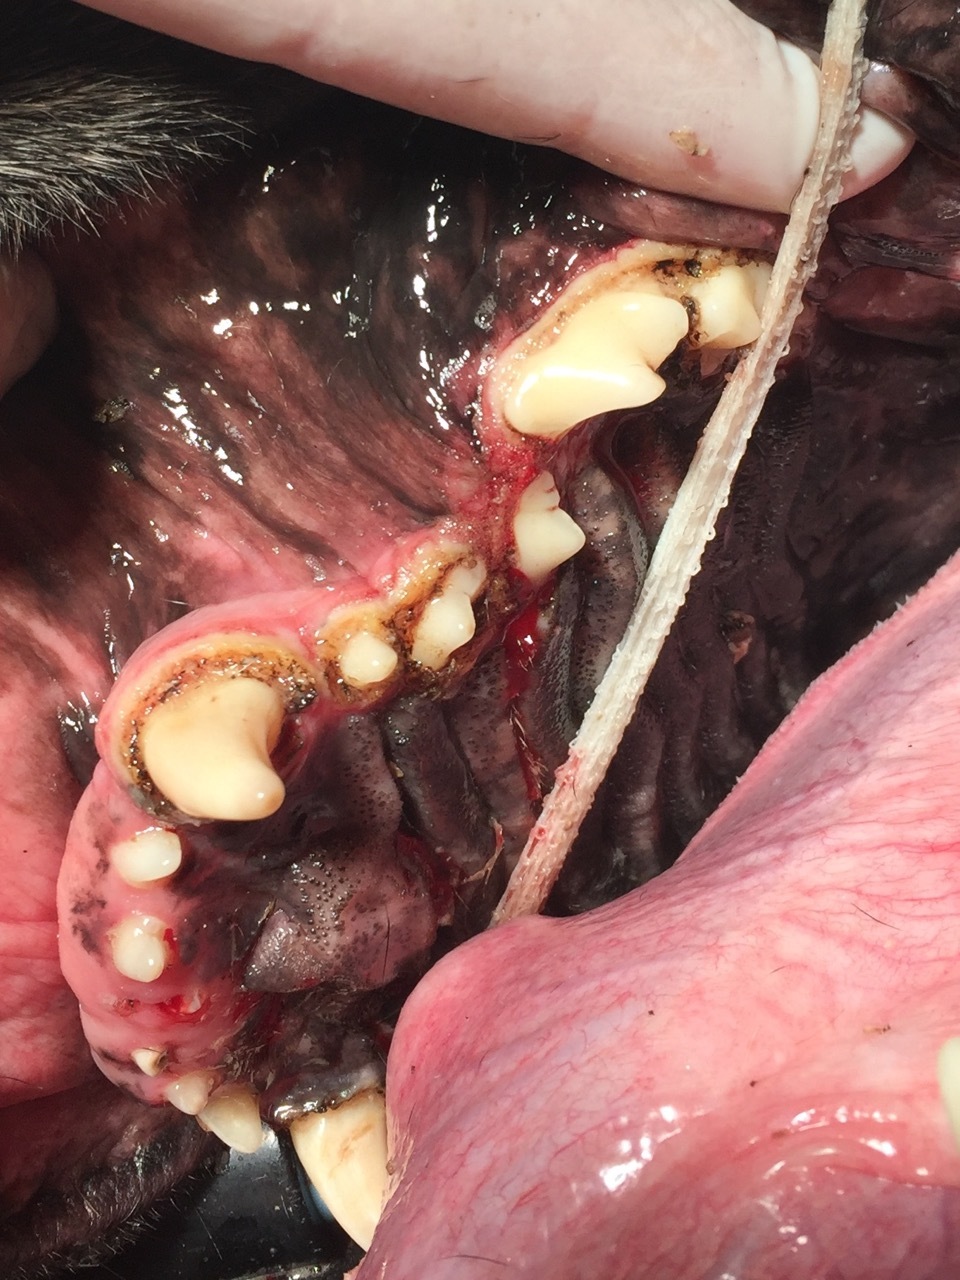

Dann sahen wir uns die Maulhöhle an, in der wir insgesamt 24 Lokalisationen am Zahnfleisch markieren konnten, die behandlungsbedürftig waren. (Abb. 1-4). Das Zahnfleisch wies sogenannte periphere odontogene Fibrome auf, die umgangssprachlich auch als Epuliden bezeichnet werden. Der Boxer, die Bordeaux Dogge, der Mops und die Französiche Bulldogge weisen hier eine Prädisposition auf, haben also eine Veranlagung zur Ausbildung dieser Tumore.

Von der Einteilung bezeichnet man die Epuliden als gutartige Zubildungen, die dem Zahnfleisch aufsitzen. Sie bilden keine Metastasen (Tochtergeschwülste) aus. Allerdings können sie erhebliche Ausmaße annehmen, wie man anhand der Abb.3 sehen kann. Die Epuliden können somit sowohl zu einer mechanischen Einschränkung beim Zermahlen des Futters als auch zu entzündlichen Veränderungen führen, dadurch erhebliche Schmerzen verursachen und sogar Zähne verdrängen. Zusätzlich konnte man in allen vier Quadranten bei Inspektor eine Gingivahyperplasie verzeichnen, die sich durch überwuchernde Zahnfleischbereiche darstellt. Teilweise werden ganze Zähne überwachsen vom Zahnfleisch, so dass hier massive Taschen entstehen, die Futterreste, Haare und anderes Fremdmaterial aufnehmen (Abb 1). Die daraus folgenden Entzündungen, die sich bis auf den tieferen Zahnhalteapparat auswirken, bedingen einen Rückgang des Knochens. Die Parodontitis ist in vollem Gange und lässt sich nur noch stoppen, aber nicht mehr heilen. Betroffene Zähne werden ab einem Furkationsbefall Grad 3 (die Wurzelaufteilung liegt gut sondierbar frei) extrahiert.